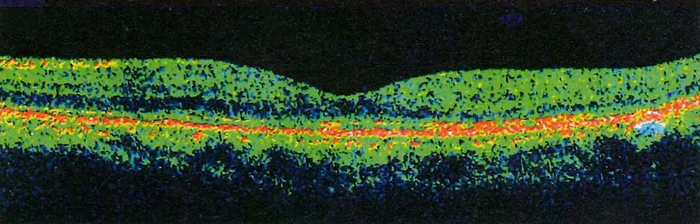

图3:光学相干断层扫描:黄斑区明显水肿、隆起

图5:接受眼内注射药物治疗后黄斑水肿消退、视力改善